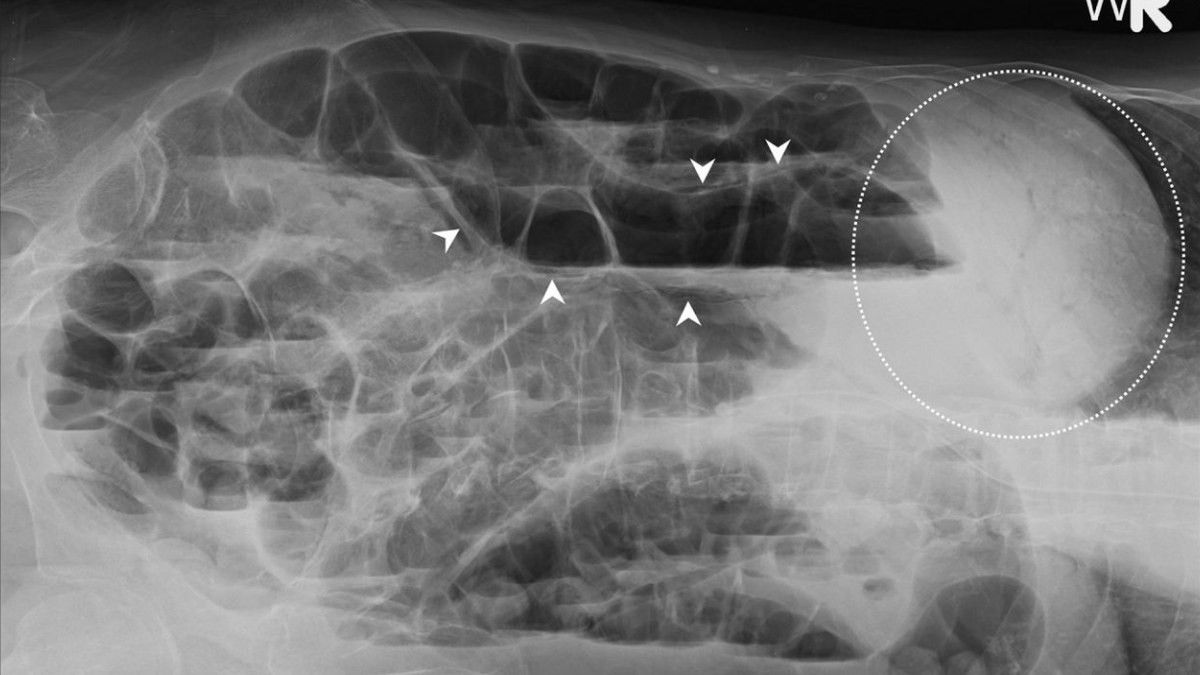

Menurut dr. Devia Irine Putri, pneumatosis adalah penumpukan gas di dinding usus. Ini salah satu kondisi gawat darurat di bidang bedah, karena usus jadi melar atau besar akibat adanya gas berlebih.

"Kami menemukan adanya kelainan usus pada pencitraan pasien dengan COVID-19. Kondisi ini lebih umum ditemukan pada pasien yang dirawat di ICU," kata Dr. Rajesh Bhayana dari Massachusetts General Hospital, Boston, Amerika Serikat.

"Kematian jaringan akibat pneumatosis diketahui dari hasil pencitraan, seperti rontgen dan CT Scan," ungkap dr. Devia.